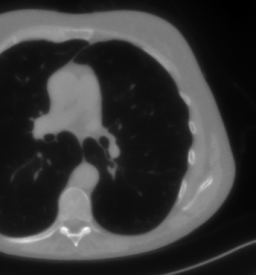

The considered images are pixel reconstructions of human abdomen, computed from full-dose acquisitions. In Figure 2 we depict one image with two zooms-in highlighting areas with different anatomical structures, such as pulmonary details, sections of ribs and low-contrast inter-costal muscles.

In all the experiments reported in 5.1, we have used the images from the data set as ground truth references.

Coherently, we simulate the tomographic projections of the ground truth images, according to a 2D fan-beam geometry, and we add to the sinograms white Gaussian noise with noise level.

To address sparse-view CT reconstructions, we considered two different protocols: the first one is a full angular acquisition with 1-degree spaced projections (we call it in the following); in the second one the scanning trajectory covers degrees and computed only projections (it is labelled as ).